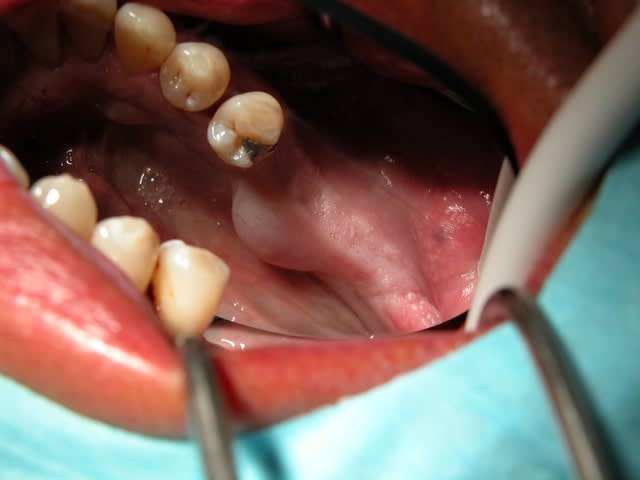

Un Taurus avec 3 lobes assez genant...

Pas facile d acces et le plancher buccal a cote.